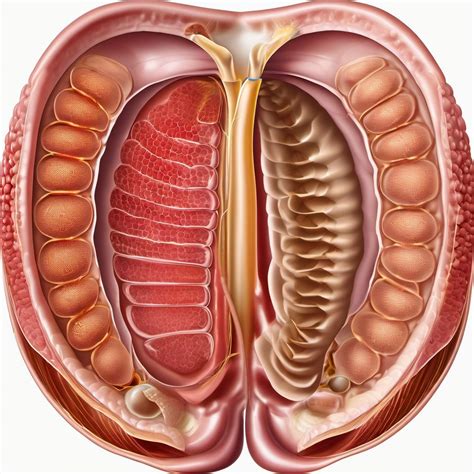

A lesion is broadly defined as any area of the skin that differs in appearance from the surrounding tissue. This can include anything from common moles and rashes to more complex structural changes. When clinicians encounter an unexplained mark—sometimes colloquially referred to under specific nomenclature like a Dieu La Foy Lesion—they must evaluate it based on several key characteristics to determine if it is benign, inflammatory, or potentially malignant.

When a physician investigates an unusual lesion, they employ various diagnostic tools to gain a clearer picture of the pathology. This process is vital to differentiate a Dieu La Foy Lesion from other common skin issues like hemangiomas, angiomas, or simple vascular malformations. The standard approach includes: